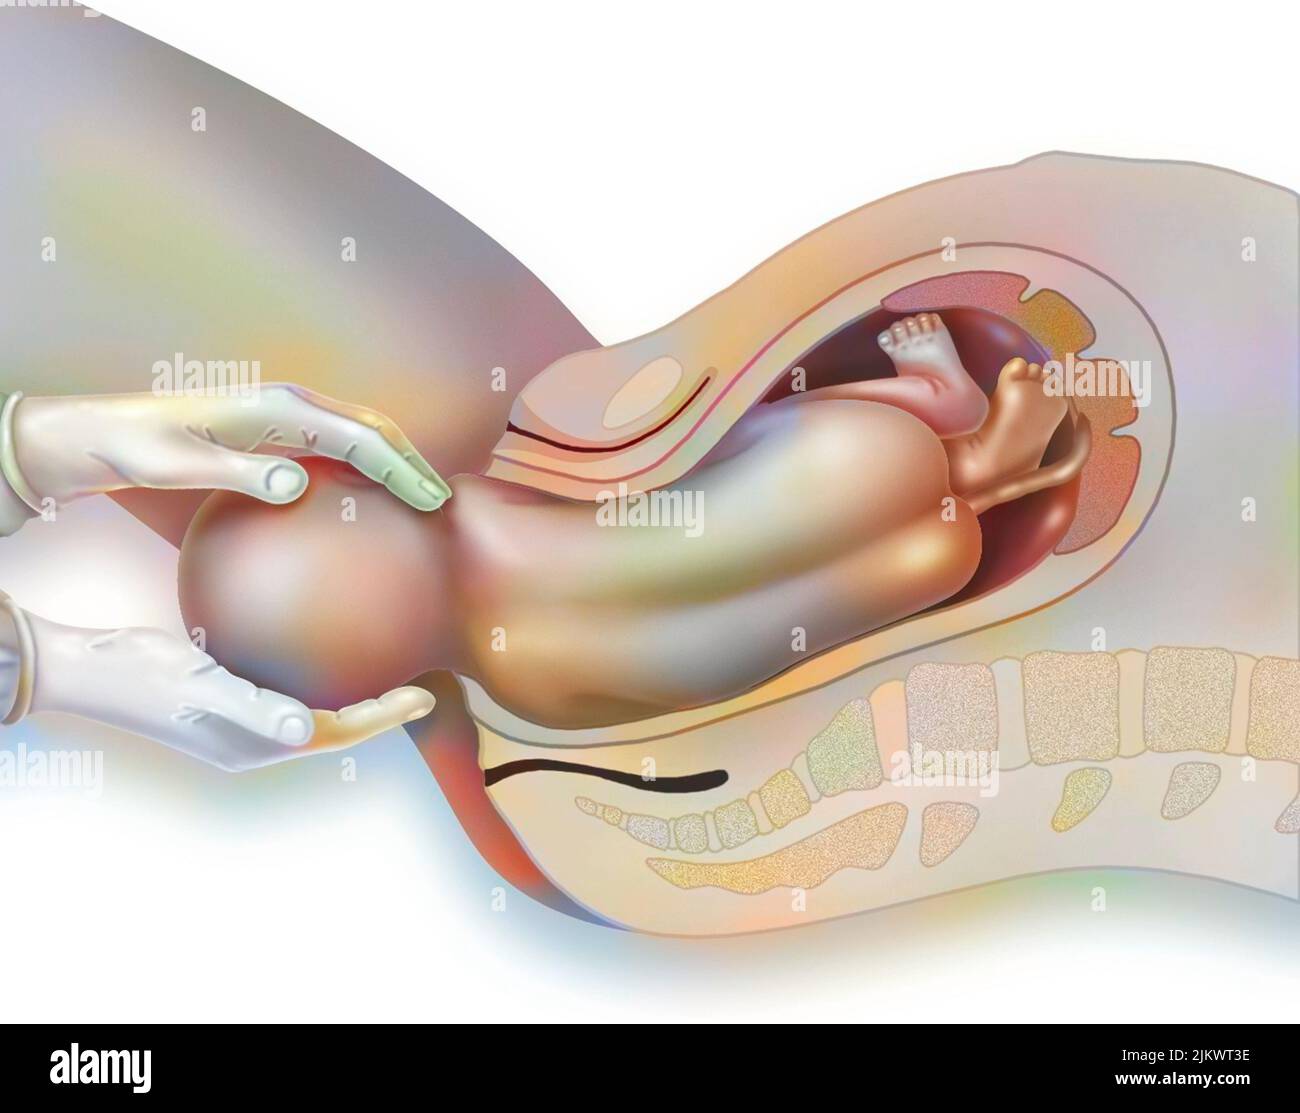

Childbirth, stage 1: the baby is engaged in the pelvis. Stock Photohttps://www.alamy.com/image-license-details/?v=1https://www.alamy.com/childbirth-stage-1-the-baby-is-engaged-in-the-pelvis-image476926081.html

Childbirth, stage 1: the baby is engaged in the pelvis. Stock Photohttps://www.alamy.com/image-license-details/?v=1https://www.alamy.com/childbirth-stage-1-the-baby-is-engaged-in-the-pelvis-image476926081.htmlRF2JKWT29–Childbirth, stage 1: the baby is engaged in the pelvis.